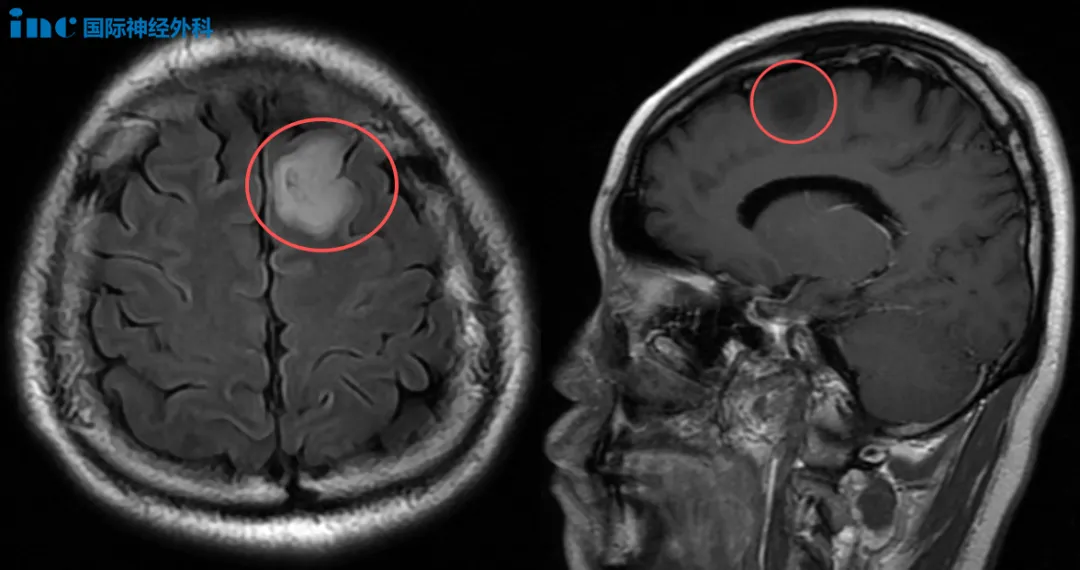

术前MRI

“必须高质量地活着!”虽然没有症状,但胶质瘤可能长大、甚至恶化,郑先生毅然决定尽早手术,以绝后患。他做出这一坚定选择的信心,正来源于对巴教授深厚的信任。

神经外科的手术治疗,从来不是一个瞬时动作,而是一个连续过程。从术前请巴教授评估、方案制定,到术中操作、术后康复,主刀是贯穿全程的灵魂人物。尤其在重大手术中,患者和家属所信赖的一直都是执刀之人——他的经验、判断与担当。

术前谈话时,巴教授表示已经通过特殊技术处理脑成像,以明确肿瘤位置及与运动神经纤维束的关系,如同绘制大脑中的地图一样。他强调,由于个体差异,术前充分了解这些信息对手术规划至关重要。“我们会竭尽所能(try the best)。”这句承诺,也给予了郑先生莫大的信心。顺利手术后,郑先生无需进ICU。